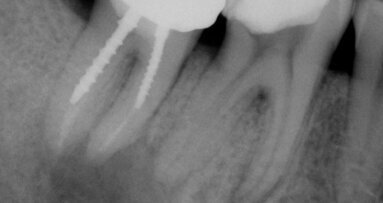

As an endodontist, I was trained to get to the root of the problem. While this is literally my job and my passion, in the past it has also been a source of ...